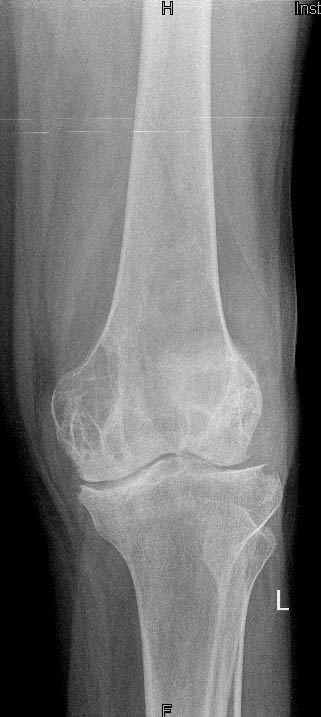

Коллеги!Окажите, пожалуйста, консультативную помощь.Мужчина, 41 год, 15 лет состоит на учете по поводу ревматоидного полиартрита, гормонзависимый (преднизолон получает нерегулярно). В процесс вовлечены крупные и мелкие суставы. 01.01.06 - без травмы наступил патологический перелом на границе н/3-с/3 бедра (перелом на фоне кистозных изменений?)

На рентгенограммах, помимо перелома, кистозные изменения на мыщелках б/берцовой кости и мыщелке бедра с другой стороны.